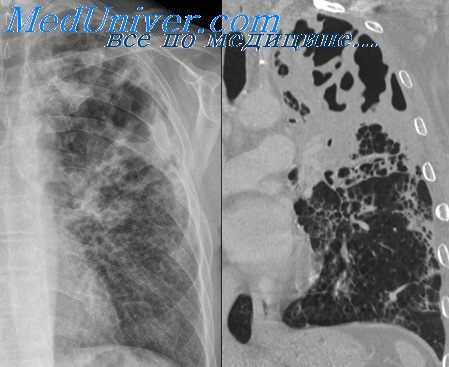

Картина, выявляемая по данным рентгенографии легких, различается в зависимости от формы бактериальной деструкции легких. В типичных случаях легочные деструкции определяются в виде полостей с горизонтальным уровнем жидкости, вокруг которых распространяется воспалительная инфильтрация легочной ткани. При плевральных осложнениях выявляется смещение тени средостения в здоровую сторону, уровень жидкости в плевральной полости, частичный или полный коллапс легкого. В этом случае целесообразно дополнение рентгенологической картины данными УЗИ плевральной полости, плевральной пункции и исследования экссудата. Бактериальную деструкцию легких требуется дифференцировать от полостной формы рака легкого, бронхогенных и эхинококковых кист, кавернозного туберкулеза. В проведении дифдиагностики, должны участвовать пульмонологи, торакальные хирурги, фтизиатры.